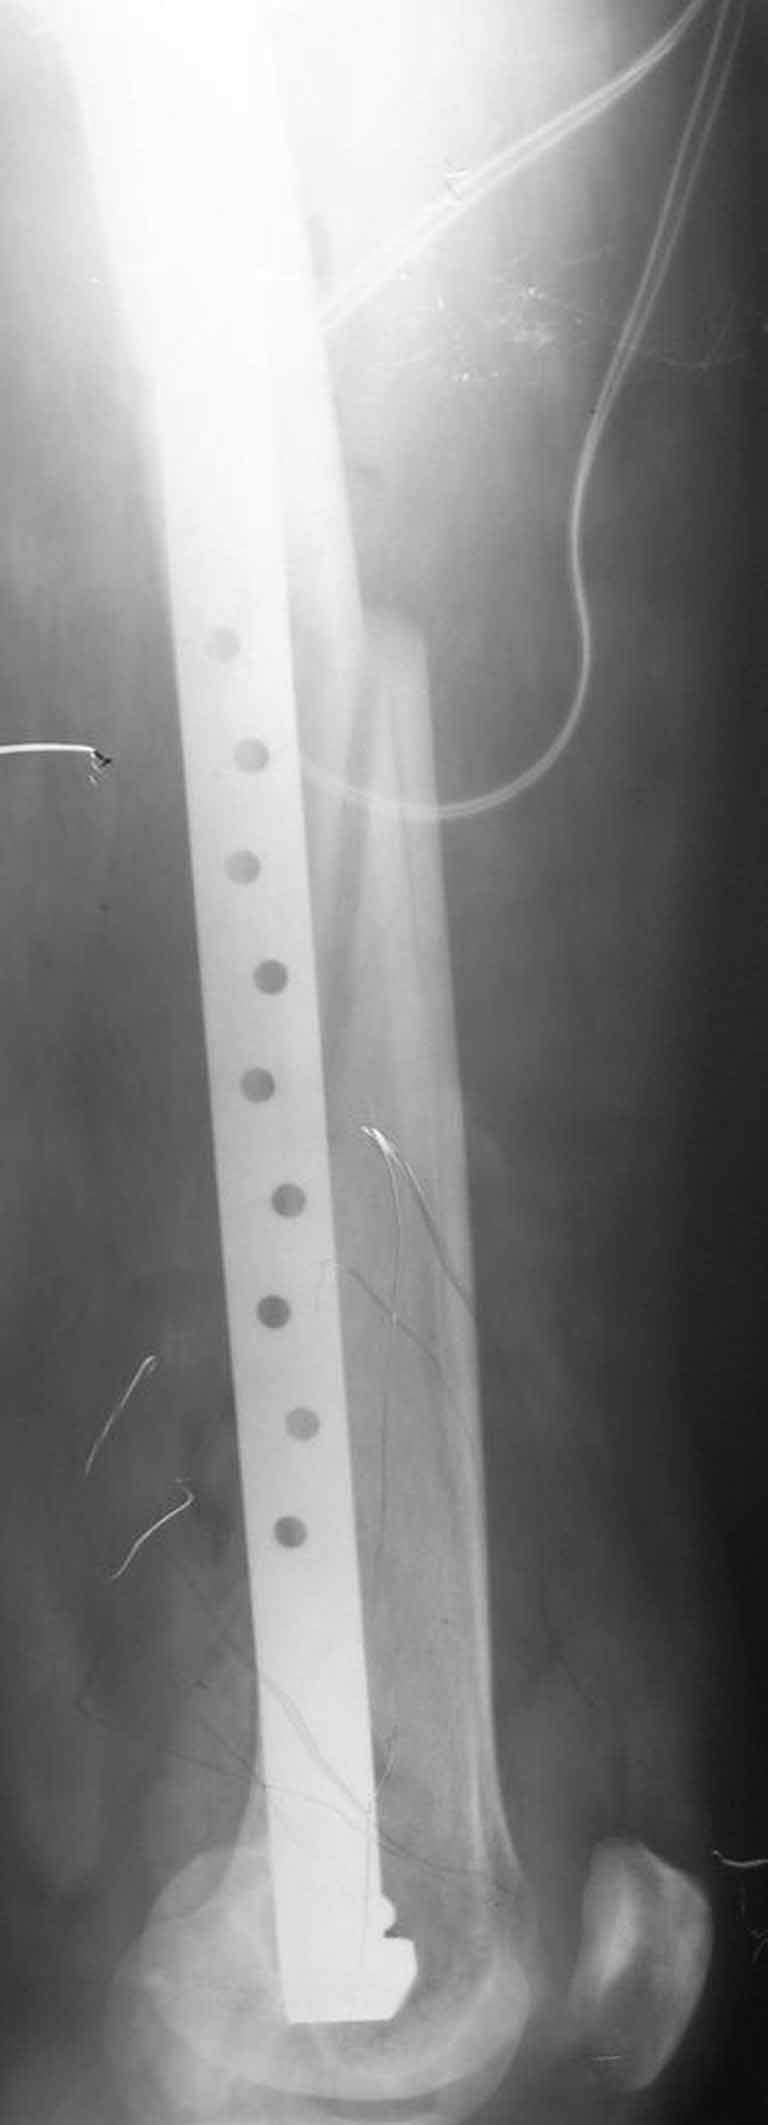

Представляю вам один из наших недавних случаев выполнения малоинвазивного остеосинтеза бедренной кости обычной пластиной 95 градусов. Длина восстановлена с помощью дистрактора (по сути это основная и б(о)льшая часть репозиции). Произведено два небольших доступа, проведена спица направитель. Рентген-контроль для подтверждения достаточной длины/оси (ЭОП использовался в другой операционной). Создание туннеля обратной стороной фиксатора. Поворот фиксатора, введение клинка по спице. Фиксация проксимального и дистального концов пластины.

Получилось очень симпатично, поздравляю и восхищаюсь мастерством.

Хотя закрытый остеосинтез блокированным гвоздем выглядит технически проще, особенно при диафизарных переломах. Не говоря о биомеханических преимуществах внутрикостного имплантата, еще меньшей инвазивности, возможности динамизации при проблемах со сращением... Стоимость гвоздей и пластин сопоставимая, на рынке есть масса отечественных предложений.

В приложении - недавний перипротезный перелом.